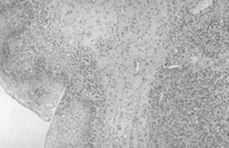

8. La presencia de componente juntural en continuidad con el tumor hace pensar en un origen vaginal de la lesión (Figs. 2 y 3).

Figuras 2 y 3.Componente juntural en continuidad con el tumor.